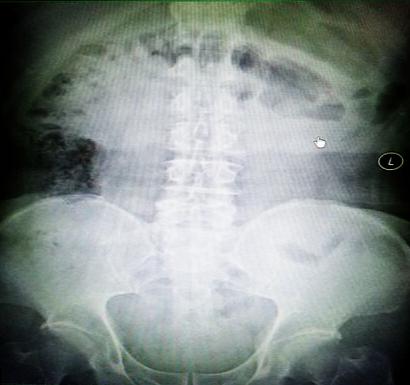

受試患者在結(jié)腸端端吻合術(shù)中,使用我司新研制產(chǎn)品達到了理想的預期效果。患者術(shù)后7天、14天X光片顯影,可降解腸道支架均能按研制設(shè)計的預期時間節(jié)點保持應(yīng)有強度,術(shù)后21天X光片顯示可降解腸道支架已完全破碎,并排出體外。在整個試驗過程中,病患無任何不良反映,耐受良好。